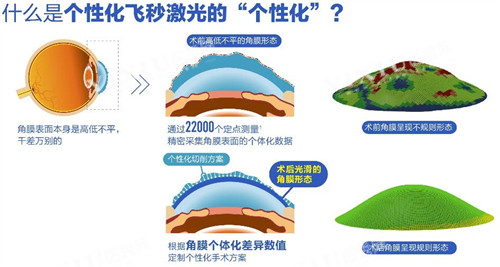

术前检查必要性:所有手术患者需完成200-300元的全套检查,包括角膜地形图、眼底照相等,以排除禁忌症。

设备优先级:优先选择搭载新一代飞秒激光设备的分院,虽费用略高,但精度与可靠性更优。